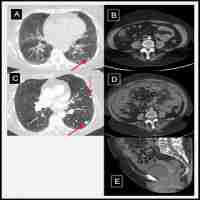

| Abstract | Introduction: Immune therapy has ushered in a new era of tumor treatment, at the expense of immune-related adverse events, including rare but fatal adverse cardiovascular events, such as myocarditis. Steroids remain the cornerstone of therapy for immune-related myocarditis, with no clear consensus on additional immunosuppressive treatment for steroid-refractory cases yet. Case report: Here we report a patient with stage IV nasopharyngeal carcinoma who developed immune-related myocarditis in the fourth course of therapy with immune checkpoint inhibitors. The patient presented with precordial discomfort with elevation of cardiac enzymes and interleukin-6, atypical electrocardiographic abnormalities and reduced left ventricular ejection fraction. Coronary computed tomography angiography excluded the possibility of acute coronary syndrome. Therapy with tofacitinib targeting the Janus kinase-signal transducer and activator of transcription signal pathway was successfully conducted since there was no significant improvement in troponin under high dose-steroid and intravenous immunoglobulin treatment. The patient recovered without major adverse cardiac events during hospitalization. Discussion: The safety and efficacy of tofacitinib in a patient with steroid refractory immune-related myocarditis was investigated, hoping to provide a basis for prospective therapeutic strategies. Tofacitinib led to remarkable remissions in primary autoimmune disease by blocking the inflammatory cascade, indicating its potential therapeutic use in immune-related adverse events. |